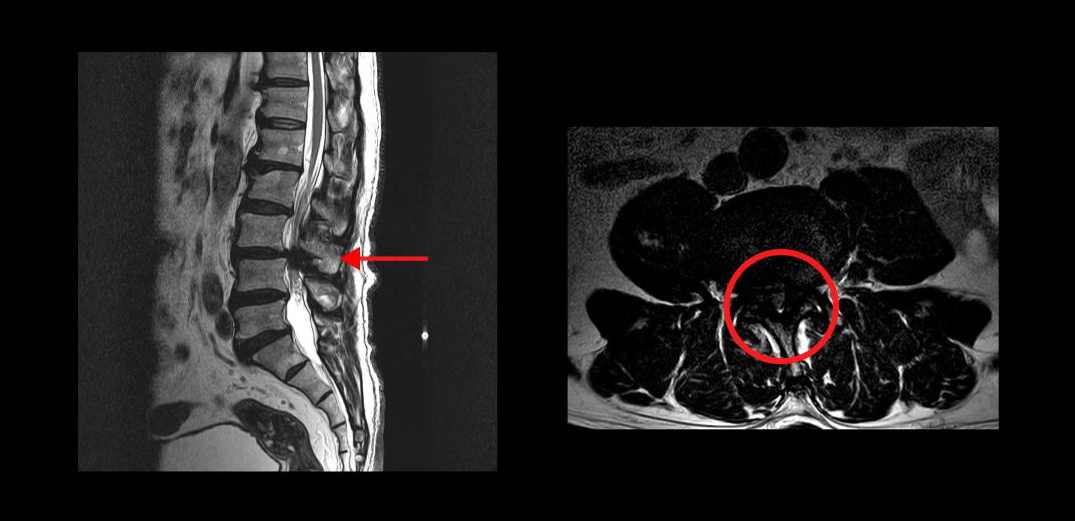

실제로 척추관이 심하게 막힌 환자분들의 케이스를 보여드리겠습니다

이분은 무려 세 마디의 척추관이 심하게 막혀있어서 거의 걷지 못하는 분입니다. MRI상 이렇게 세 마디의 척추관이 심하게 막힌 것이 보이실 겁니다. 이분은 무려 25년간 허리통증과 협착증 증상으로 고생하셨습니다. 그런데 서울 최상급 대학병원에서는 여러 마디가 안 좋으니 어려운 수술이고 수술의 실익이 없다는 말을 들으셨고, 서울 유명 척추전문병원에서는 세 마디를 한번에 수술할 수 없으니까 3주에 걸쳐 세 번의 수술을 하자는 말을 들으셨습니다.

또 다른 한 분은 척추관이 심하게 막혀있는 중심성 척추관협착증 환자분입니다. MRI를 보시면 한 마디가 심하게 막혀있죠. 이분은 10년 이상 협착증 증상을 앓다가, 결국 걷기만 하면 다리에 힘이 빠져버려서 아무데라도 주저 앉아야 하는 극심한 신경성 파행 증상을 겪으셨습니다. 서울의 유명 대학병원에서 수술을 하기로 했지만, 결국 심장 문제 때문에 수술을 못 받으셨습니다.